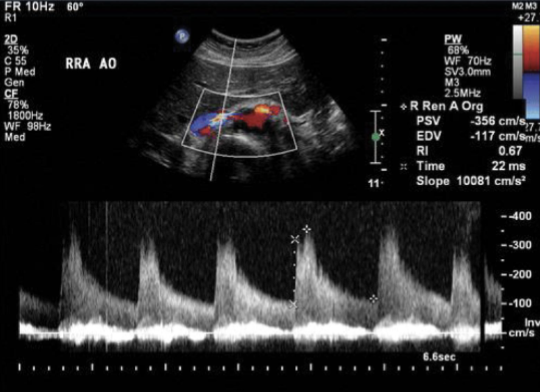

A Doppler waveform from which of the following vessels would be expected to be 'nonresistive' with high diastolic flow, indicating a need for constant perfusion?

renal artery

Select the Doppler method most commonly used in the abdomen.

pulsed wave

The arrow is demonstrating which of the following vascular structures?

right renal artery